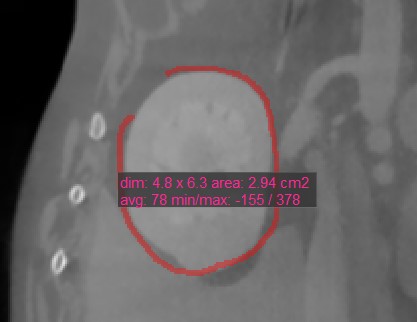

Polygon

../_images/image76.jpg

Users can create, measure and mark custom rounded areas on the active image slice by using the Polygon tool.

Select the Polygon tool and assign it to one of the available mouse buttons. Start the measurement by placing points on the active image slice. As the user places the points, the software automatically connects them and creates the rounded shape.

Complete the measurement by manually closing the path, or double-click when placing the last point to automatically close it. All available measurement values are displayed alongside the measurement.

Modify the marked area by moving one of the points describing the shape using the Default tool.